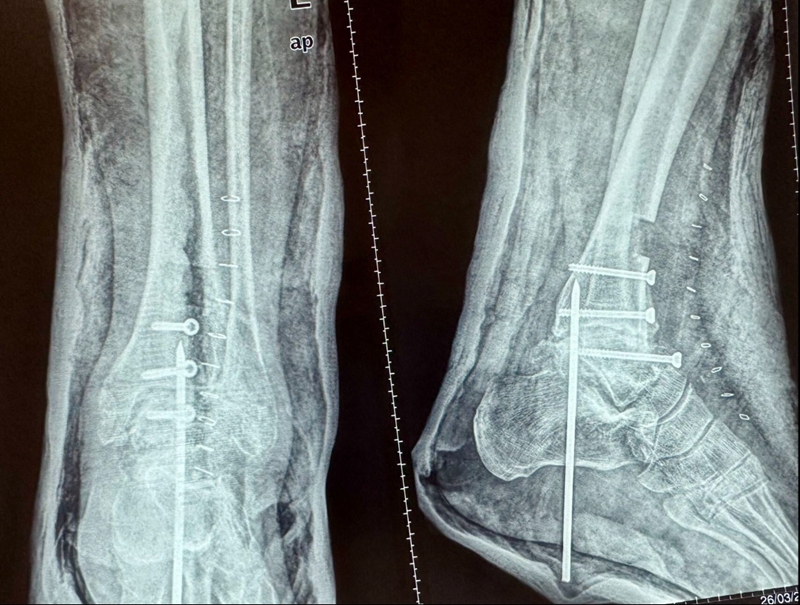

病例报告之二,xx,男,56岁,左踝创伤性关节炎。左踝崴伤6年,疼痛加剧3年。切口显露同前。

手术前资料